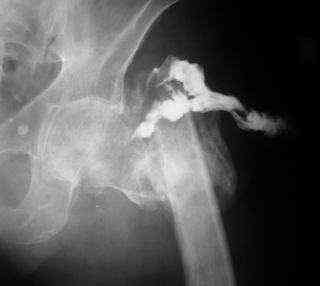

Вот снимки по свежей ситуации, парень 19 лет, длинный оскольчатый перелом бедра от шейки до в-с/3. давно уже ходит на своих ногах.

Представленные Вами рентгенограммы действительно являются примером качественной фиксации спице-стержневым аппаратом. Они, как ни что другое, многое иллюстрируют.

Кроме того, было бы ошибкой ставить знак равенства между нашим и Вашим пациентами. Они не только не похожи, разница между ними просто огромная. Говорю это не для того, чтобы задеть Вас или обидеть. Ни в коем случае. Просто теперь я понимаю, что Ваше мнением строится на простом преломлении Ваших подходов к лечению пациентов со свежими переломами, на ситуацию, абсолютно несопоставимую, подобную нашей.